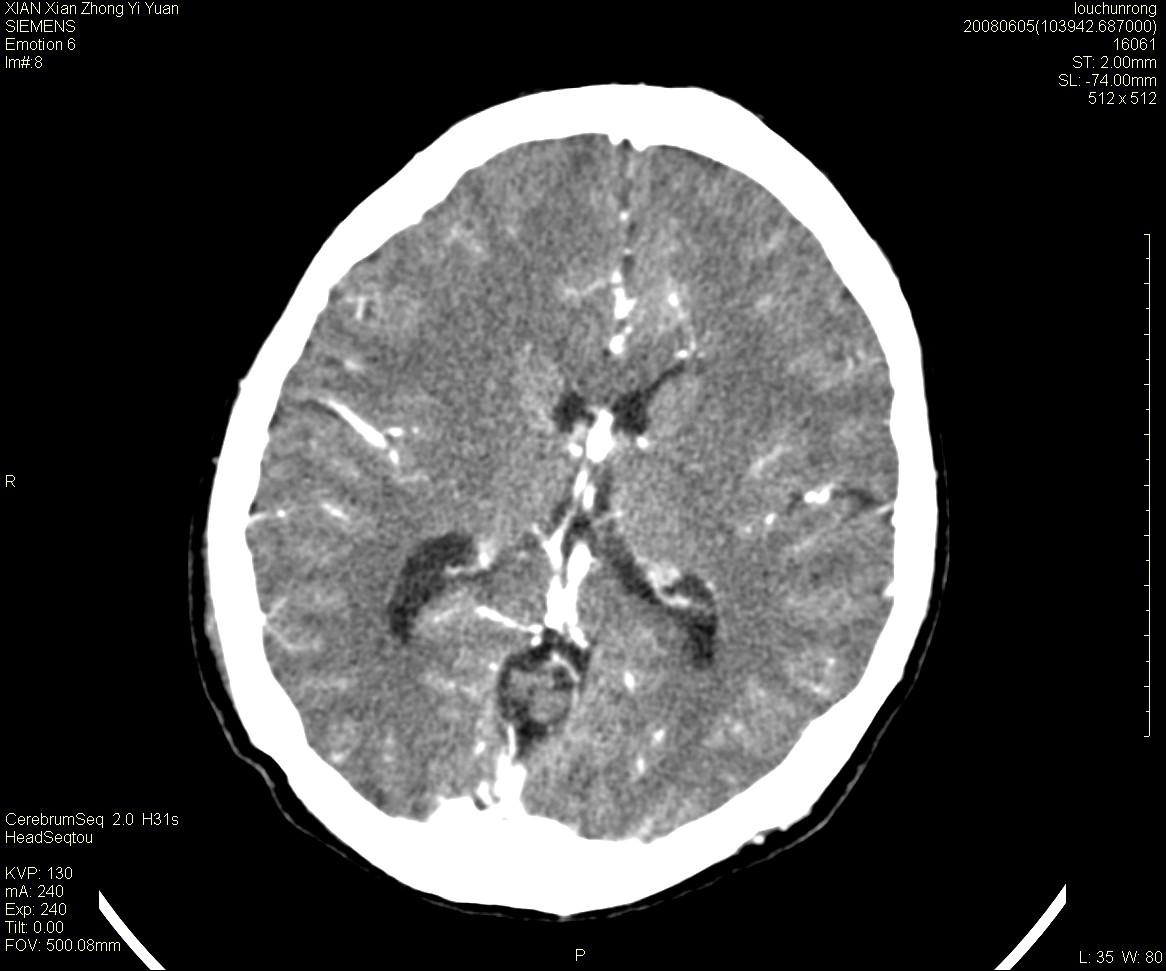

标题: CT13860:F52Y,,头外伤致头晕半天,以前无不适。 [打印本页]

标题: CT13860:F52Y,,头外伤致头晕半天,以前无不适。

层厚2mm。

大家看左额叶大脑镰旁高密度影

中线附近、枕叶近枕骨处及脑内多发点条状强化影,考虑血管异常?

大脑大静脉池内的密度不均,双侧脑室增宽,我看右异常这块。战友们看看

侧脑室前角变形、变窄,考虑侧脑室粘合;余未见明显异常。